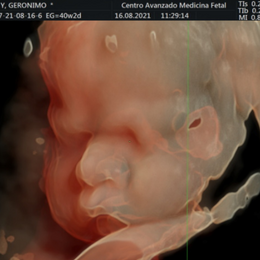

- Las formas nuevas de ecografía pueden proporcionar imágenes en 5-D.